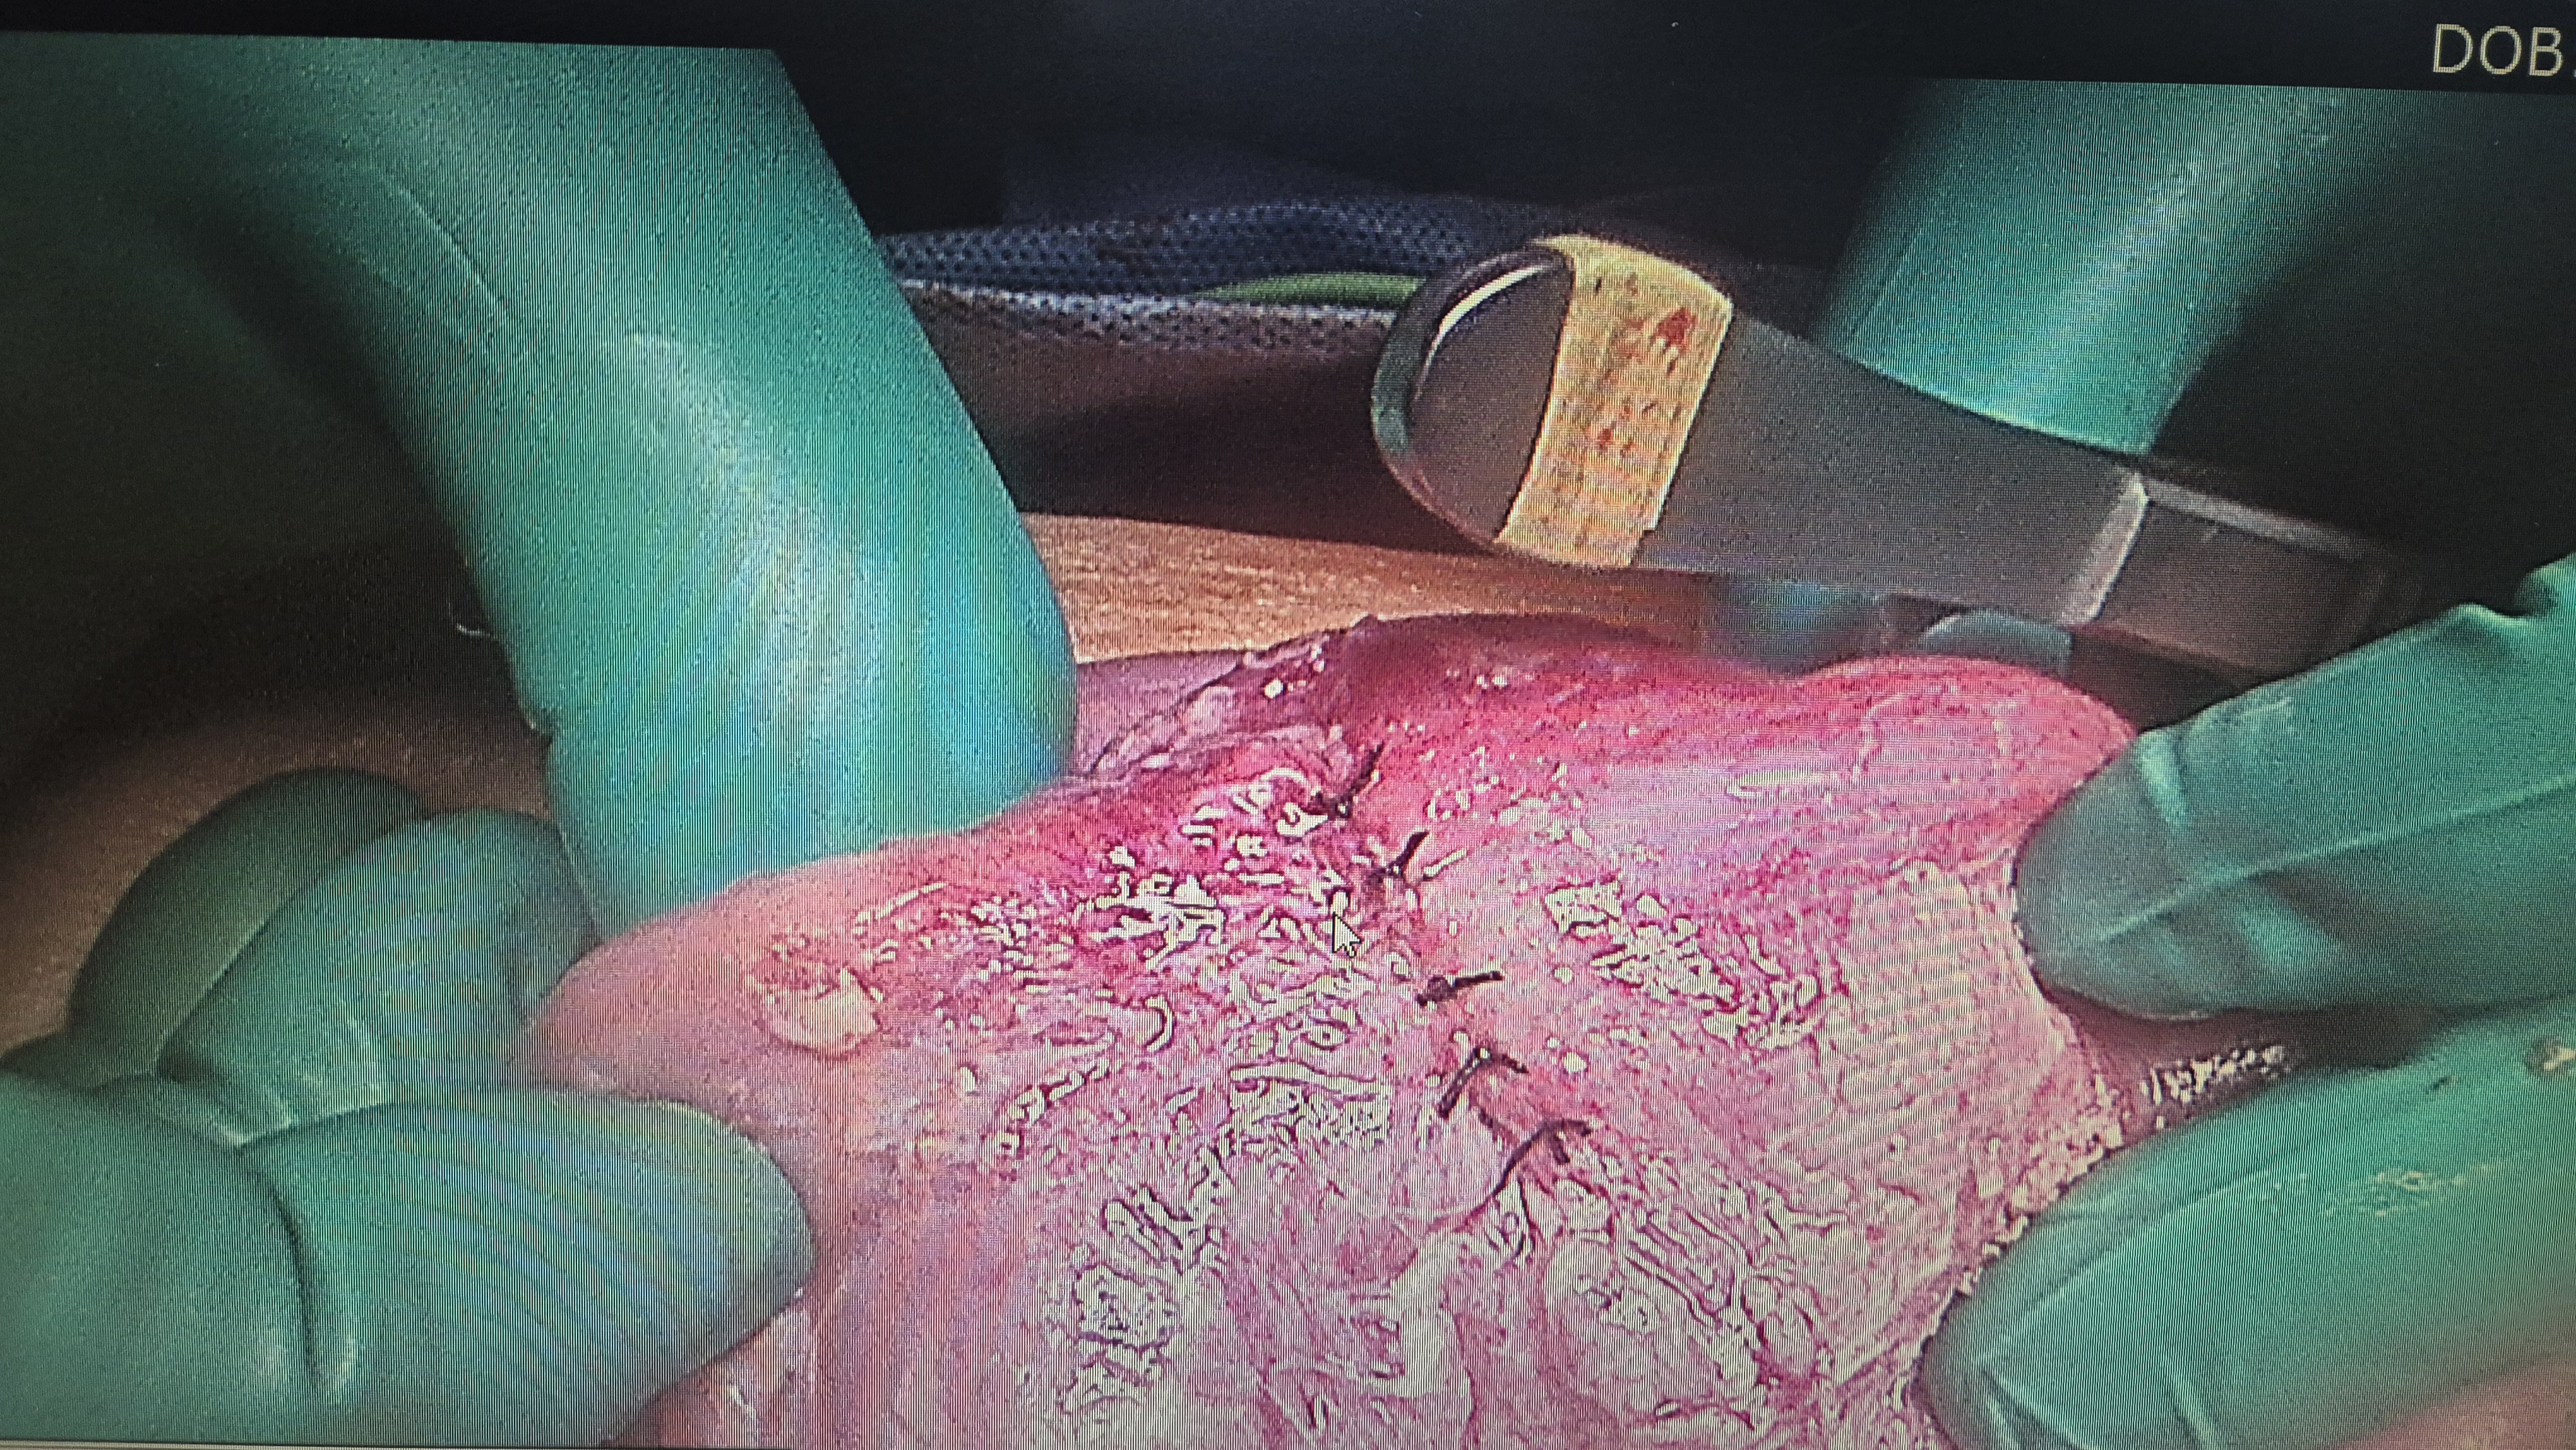

소장천공을 확인.

봉합을 시행.